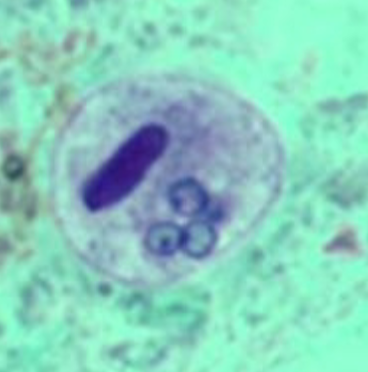

Leishmania spp.

Leishmania spp.